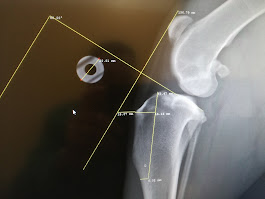

La radiologia è uno strumento diagnostico fondamentale che ci permette di osservare in modo non invasivo l’interno del corpo di cani e gatti, aiutandoci a individuare rapidamente eventuali problemi ossei, articolari, toracici o addominali.

Presso la nostra clinica disponiamo di apparecchiature radiografiche digitali di ultima generazione, che garantiscono immagini ad alta definizione e una riduzione significativa delle dosi di radiazioni. Questo ci consente di ottenere diagnosi precise in tempi brevi e con il massimo comfort per il paziente.

• Valutare fratture o traumi ossei